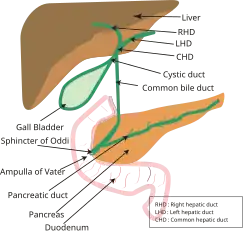

Bile is produced by the liver, and serves to eliminate cholesterol and bilirubin from the body, as well as emulsifying of fats to make them more soluble in water and aid in their digestion. Bile is formed in the liver by hepatocytes (liver cells) and excreted into the common hepatic duct. Part of the bile is stored in the gall bladder because of back pressure (exerted by the sphincter of Oddi), and may be released at the time of digestion. The gallbladder also concentrates the bile by absorbing water and dissolved salts from it. All bile reaches the duodenum (first part of the small intestine) through the common bile duct and the ampulla of Vater. The sphincter of Oddi, located at the junction of the ampulla of Vater and the duodenum, is a circular muscle that controls the release of both bile and pancreatic secretions into the digestive tract.[1]

The biliary tree is normally relatively free of bacteria because of certain protective mechanisms. The sphincter of Oddi acts as a mechanical barrier. The biliary system normally has low pressure (8 to 12 cmH2O)[9] and allows bile to flow freely through. The continuous forward flow of the bile in the duct flushes bacteria, if present, into the duodenum, and does not allow the establishment of an infection. The constitution of bile—bile salts[1] and immunoglobulin[2] secreted by the epithelium of the bile duct also has a protective role.

In ascending cholangitis, it is assumed that organisms migrate backwards up the bile duct as a result of partial obstruction and decreased function of the sphincter of Oddi.[1] Other theories about the origin of the bacteria, such as through the portal vein or transmigration from the colon, are considered less likely.[1]